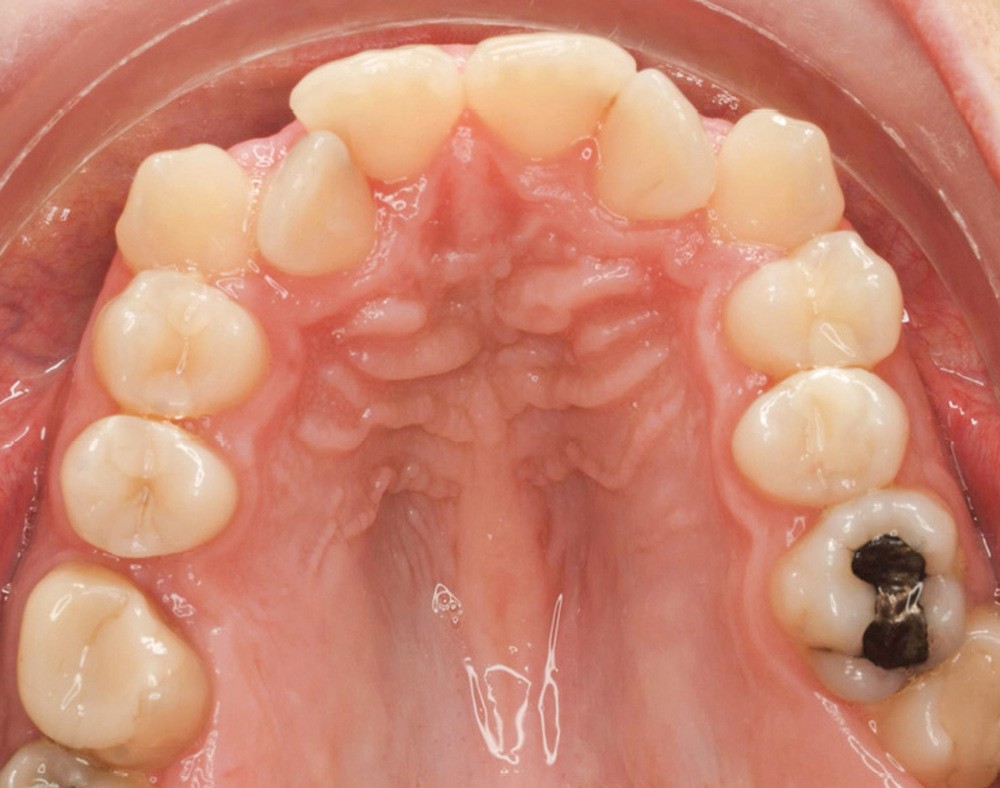

Diagnostic (fig. 1a-g)

La patiente présente une classe III squelettique dans un contexte hyperdivergent associée à une endoalvéolie maxillaire, un articulé inversé antérieur, une rétroversion incisive maxillaire, des rapports de classe I canine bilatérale, une absence de 16 et 36.

Au niveau esthétique, le profil est rectiligne. La lèvre supérieure est plus effacée, en retrait par rapport à la lèvre inférieure. De face et de profil, la mandibule paraît massive et le maxillaire effacé : le manque de soutien de la lèvre supérieure contribue à cette impression.

Le sourire est étroit, dégradé par les malpositions dentaires.

Au niveau fonctionnel, il existe un pro-glissement mandibulaire et un articulé inversé antérieur. Le profil téléradiographique montre en occlusion des rapports labiaux et un profil de classe III plus marqué que sur photographies.